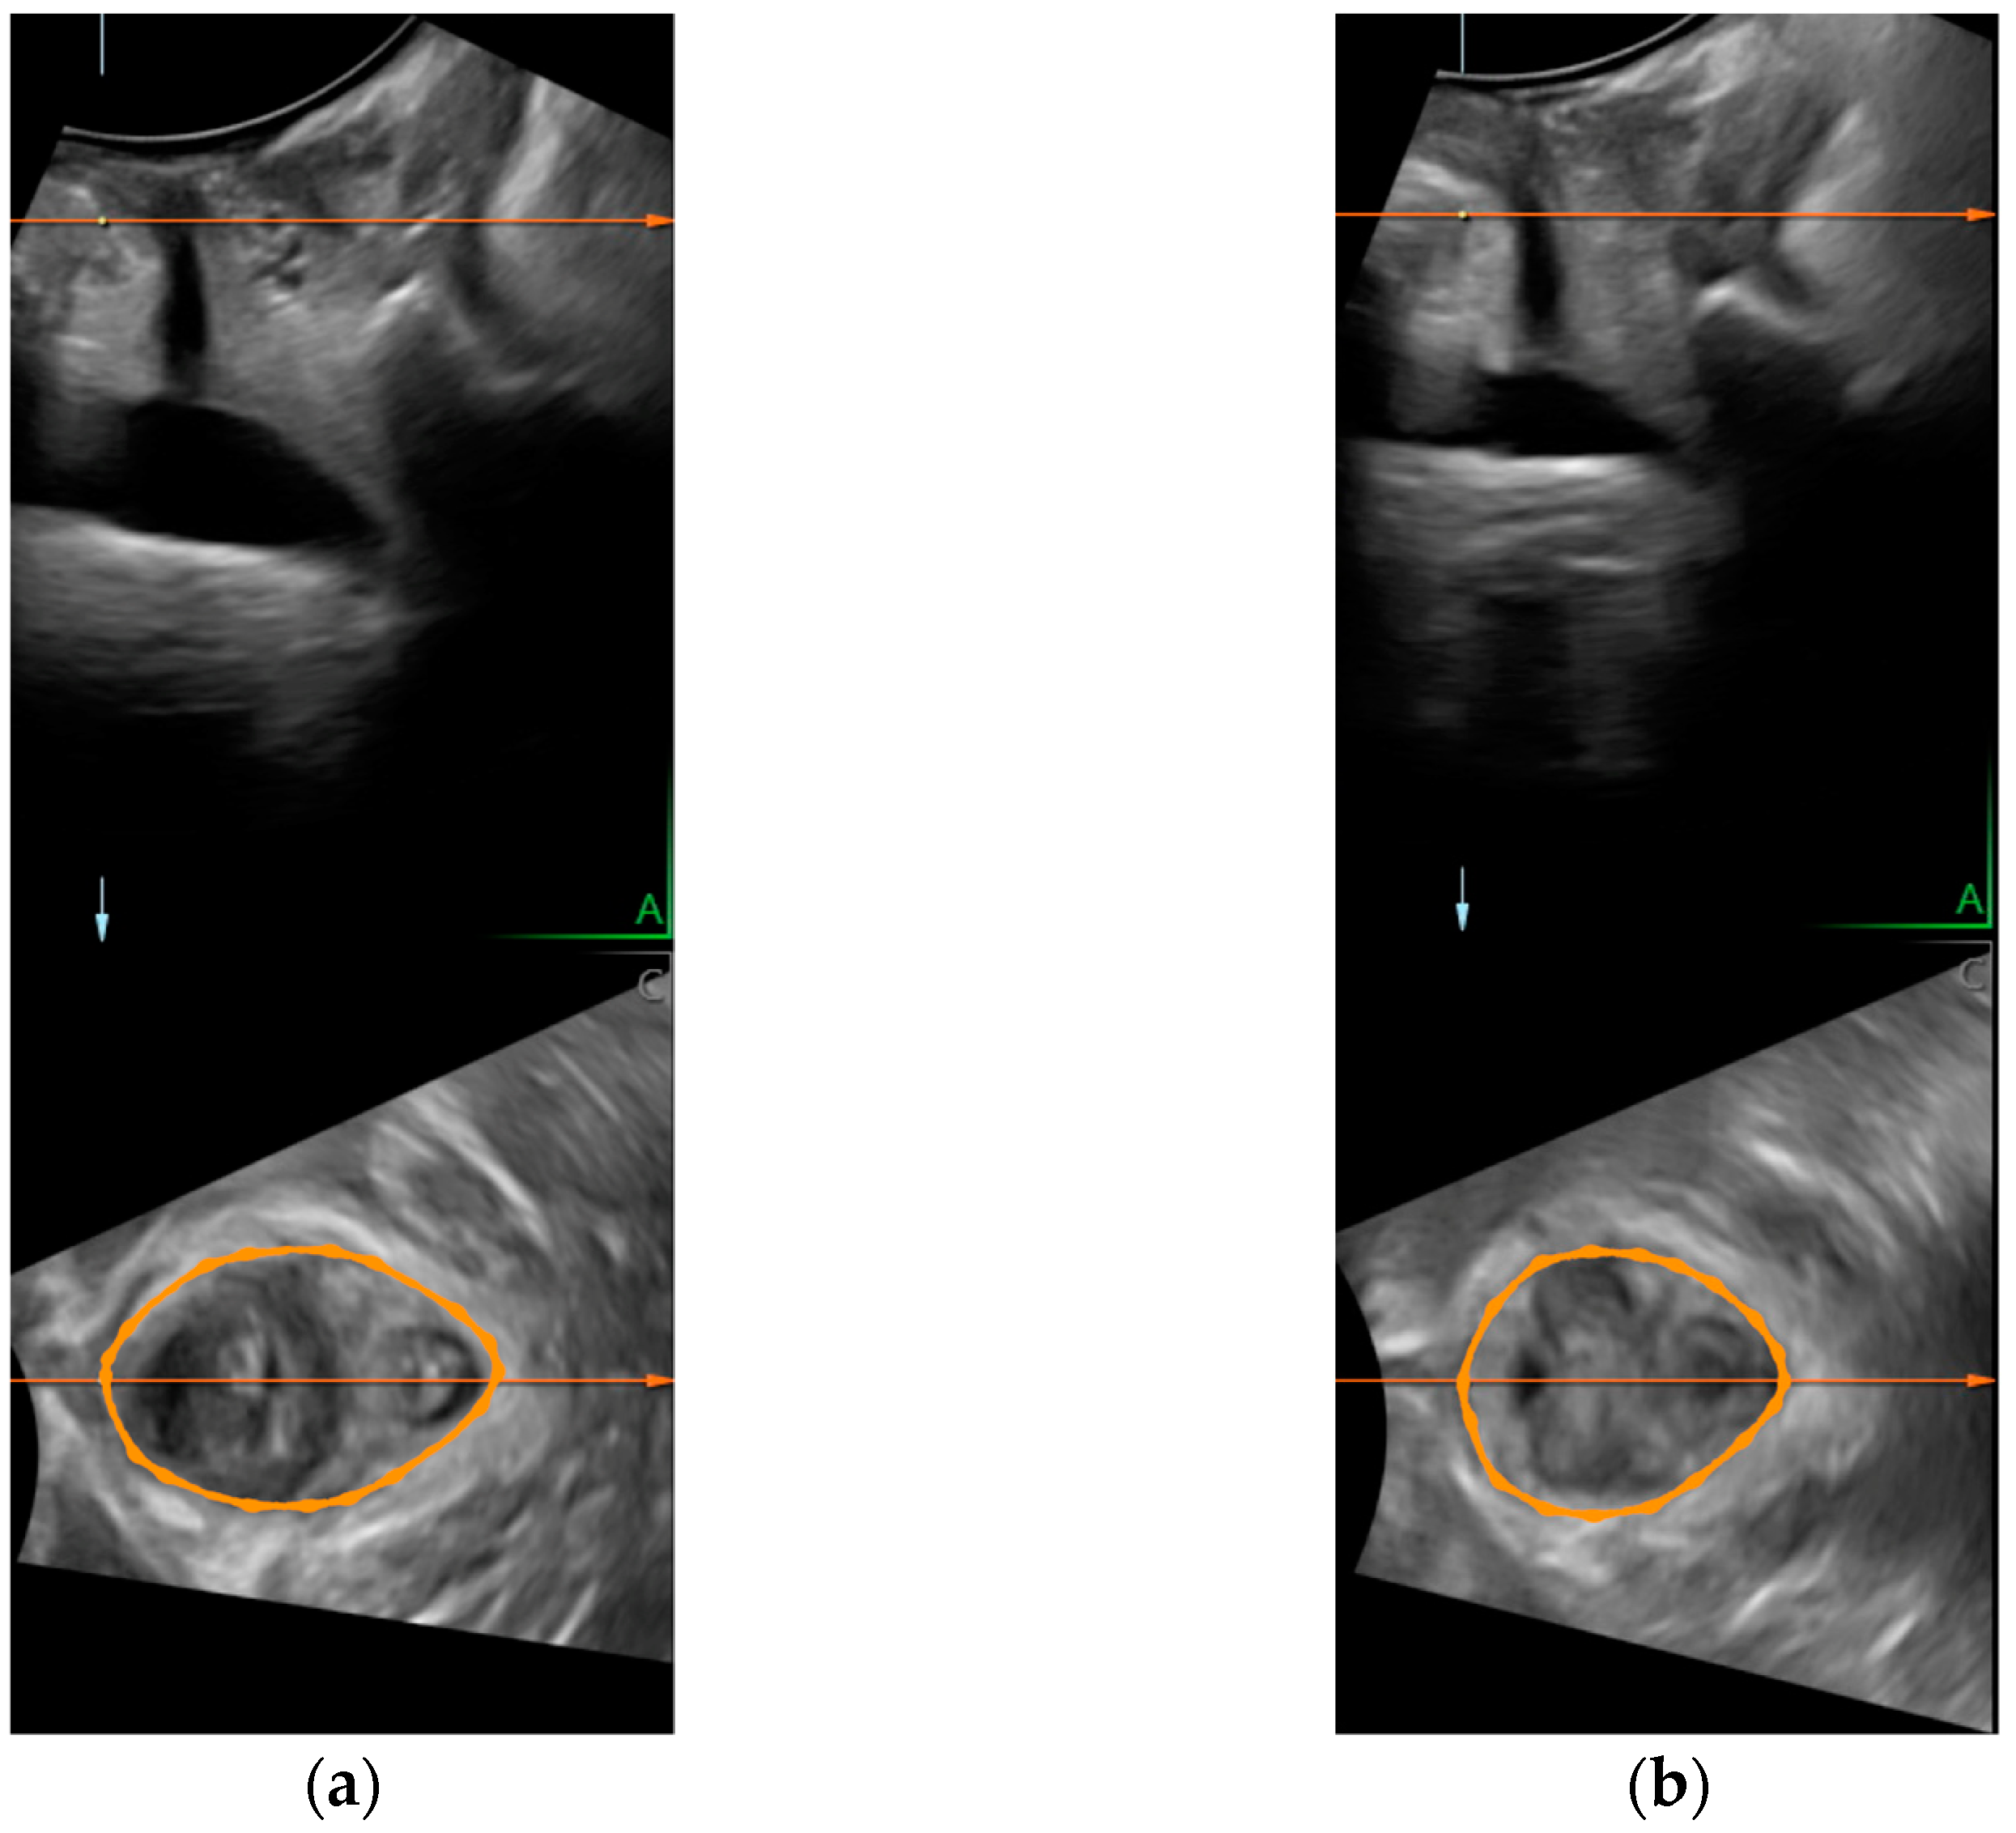

- Dietz, H.P.; Shek, K.-L.; Clarke, B. Biometry of the Pubovisceral Muscle and Levator Hiatus by Three-Dimensional Pelvic Floor Ultrasound. Ultrasound Obstet. Gynecol. 2005, 25, 580–585. [Google Scholar] [CrossRef] [PubMed]